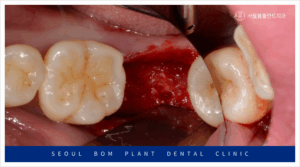

오금역치과 서울봄플란트에서는

아래턱 오른쪽 두 번째 어금니(#47)의 발치 후,

소파 작업을 철저히 진행하였습니다.

소파 작업은 임플란트 치료에서

매우 중요한 단계입니다.

만약 발치 후 염증 조직이 남아있을 경우,

잇몸뼈의 회복이 지연되고,

임플란트의 결합을 방해할 수 있습니다.

결국, 임플란트 주변에 다시 염증이

생길 위험이 있기 때문에,

꼼꼼한 소파 작업이 필수적입니다.